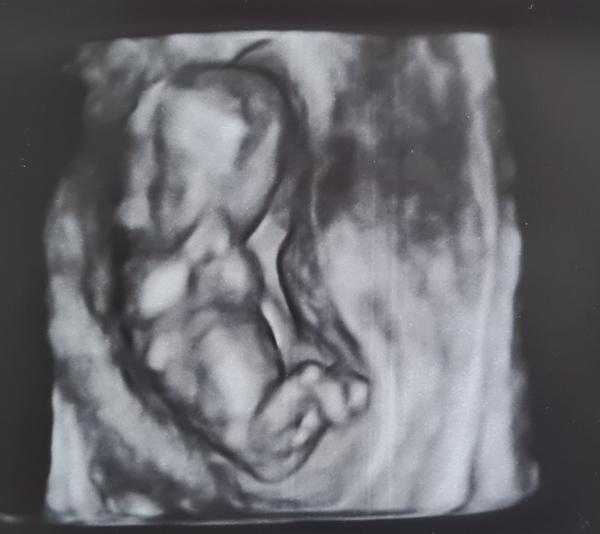

Pohlaví miminka - poznáte ho?

@makronka222 Ruce dokážu lokalizovat, ty mi doktorka na fotce ukázala 🙂. Nohy jsem neviděla, doufám, že je má :D. Já osobně vidím jen rozmazané fleky, ale třeba tu má někdo zkušené oko 🤷♀️.

Z tyhle nekvalitni fotky asi tezko neco vyhledas. Muze tam dole byt ruka, snura, nohy krizem...